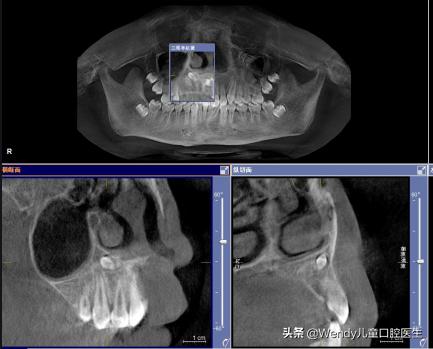

前天小泽妈带着小泽来看牙,乳牙按时掉了可惜新长出的恒牙怎么看都不对劲,形态怪异,一般这种情况首先考虑多生牙,建议拍摄全景片。果不其然,新长出的的确是多生牙,除外还发现颌骨里长了另一颗倒置的多生牙,这颗多生牙斜着挡在恒牙的上方,对恒牙萌出一定有影响,建议拔除。

对于埋伏的多生牙,如果影响恒牙的发育,萌出以及排列,在不损伤恒牙胚的情况下也应尽早拔除。

多生牙的确诊以及治疗拔除都需要在X线片下才能明确,常见的X线片有根尖片,全口曲面断层片和CBCT。